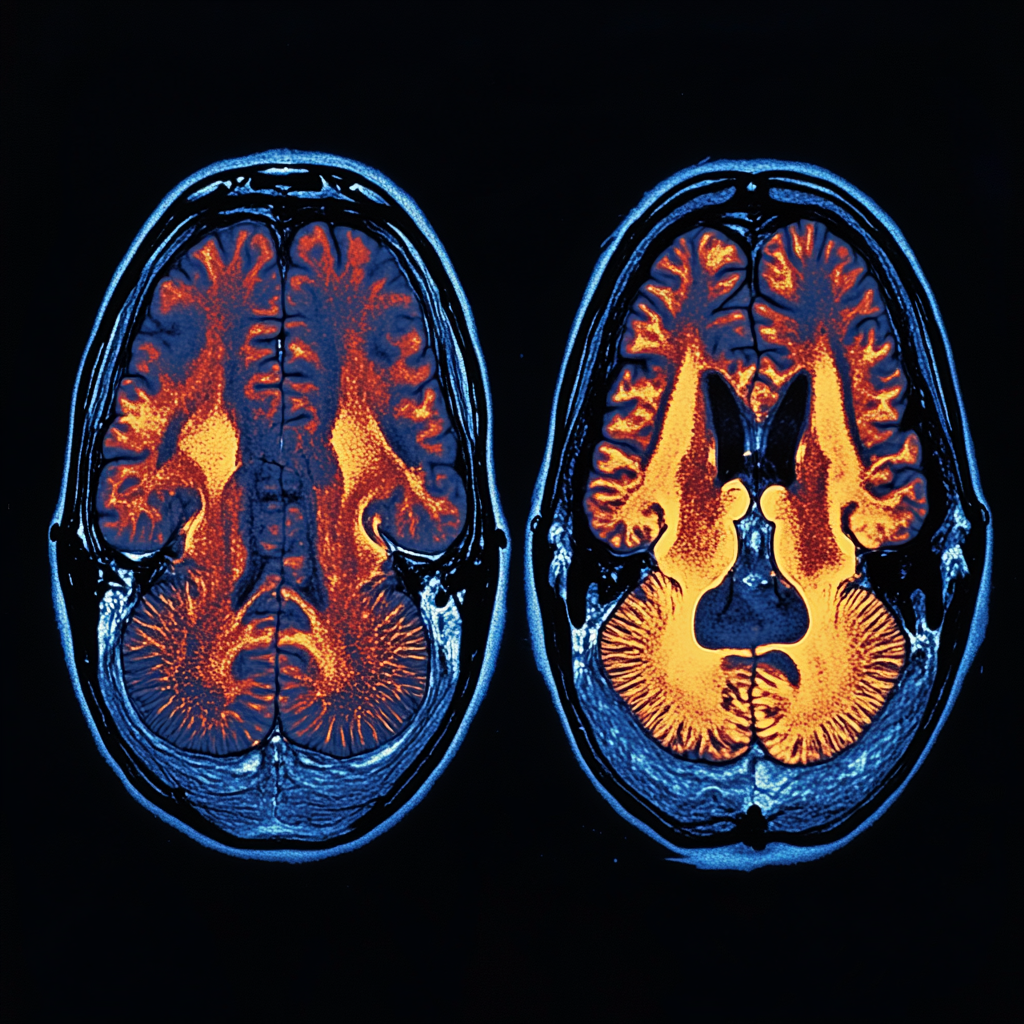

Sleep deprivation significantly impacts brain function and cognitive performance